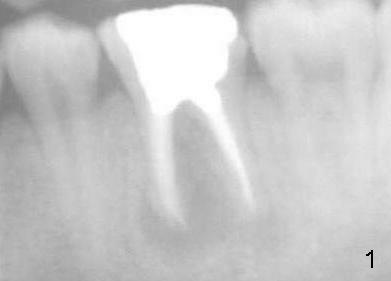

A 22-year-old man requested extraction of the tooth #19 (Fig.1).  X-ray was taken 3 and 8 months post extraction, respectively (Fig.2,3).  A 6x17 mm Tatum tapered implant was placed (Fig.4,5). A 5 mm (in diameter) 0 degree unipost (5 mm in height) was prepared 7 months after implant placement. Due to limited space, time was spent for extraoral and intraoral reduction of the abutment.

It appears that there is no bone resorption in height for patients at young age.  For their implant restoration, a shorter abutment (3 mm long, for example) should be fabricated to save precious clinical time.